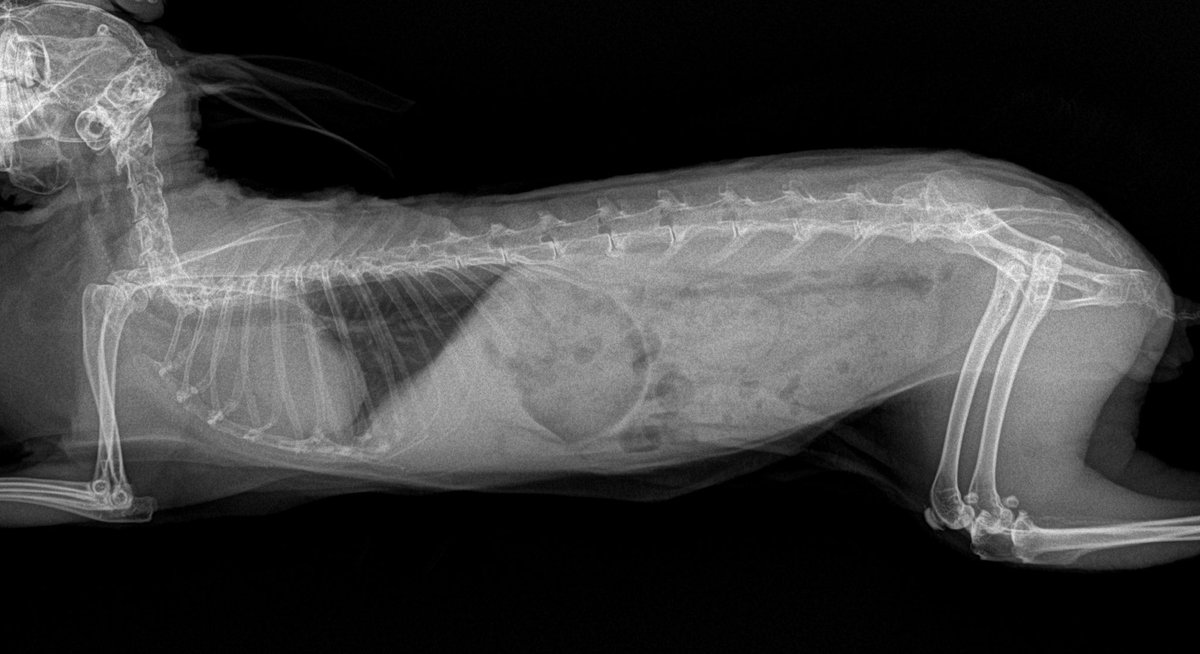

うさぎの病院 つくば院長。日々の診察をしながらうさぎや獣医師に関することを発信しています🐰うさぎ育成ゲーム「いつも、うさぎと一緒なら」の獣医師のモデルになっているかも⁈病院のインスタでも情報発信中!お仕事のご依頼はDMもしくは下記リンクにて✉️尚、飼育相談等はお受けしておりませんのでご了承下さい。